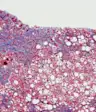

当丙肝成为一种慢性感染,这意味着它已经在体内存在多年,未经治疗,它可能会导致肝脏疾病(对任何一种阻止人体重要器官正常运转的疾病的统称)。

这可能导致肝硬化,使肝脏难以正常工作,肝癌甚至肝功能衰竭。肝脏有许多重要的功能,包括:产生蛋白质;分解食物中的营养素;储存维生素、矿物质和糖,以防止营养短缺;产生胆汁和清除血液中的细菌以防止感染。这就是为什么丙肝造成的损害会如此严重。

虽然丙肝病毒可能是无声的,但当它在你的系统中停留太久时,它就会变得致命。在体内待得太久会造成损害,可能会导致肝硬化(多年损伤导致肝脏瘢痕)、肝病和肝癌等主要问题。